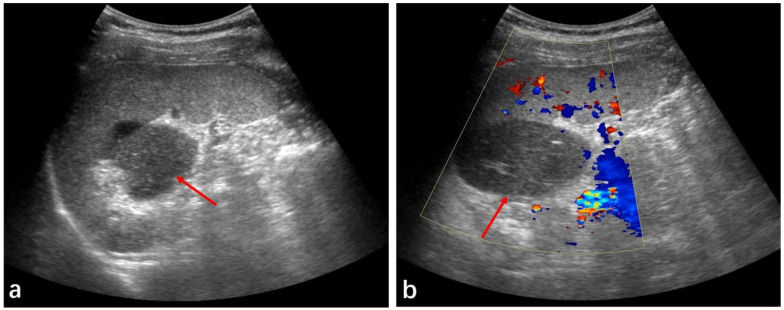

(a) Ultrasound showed a solid mass at the splenic hilum (red arrow). (b) Color Doppler showed no significant blood flow (red arrow).

Abdominal Sonography (Day 12): Large, well-defined solid mass with low inhomogeneous echogenicity, no blood flow observed.